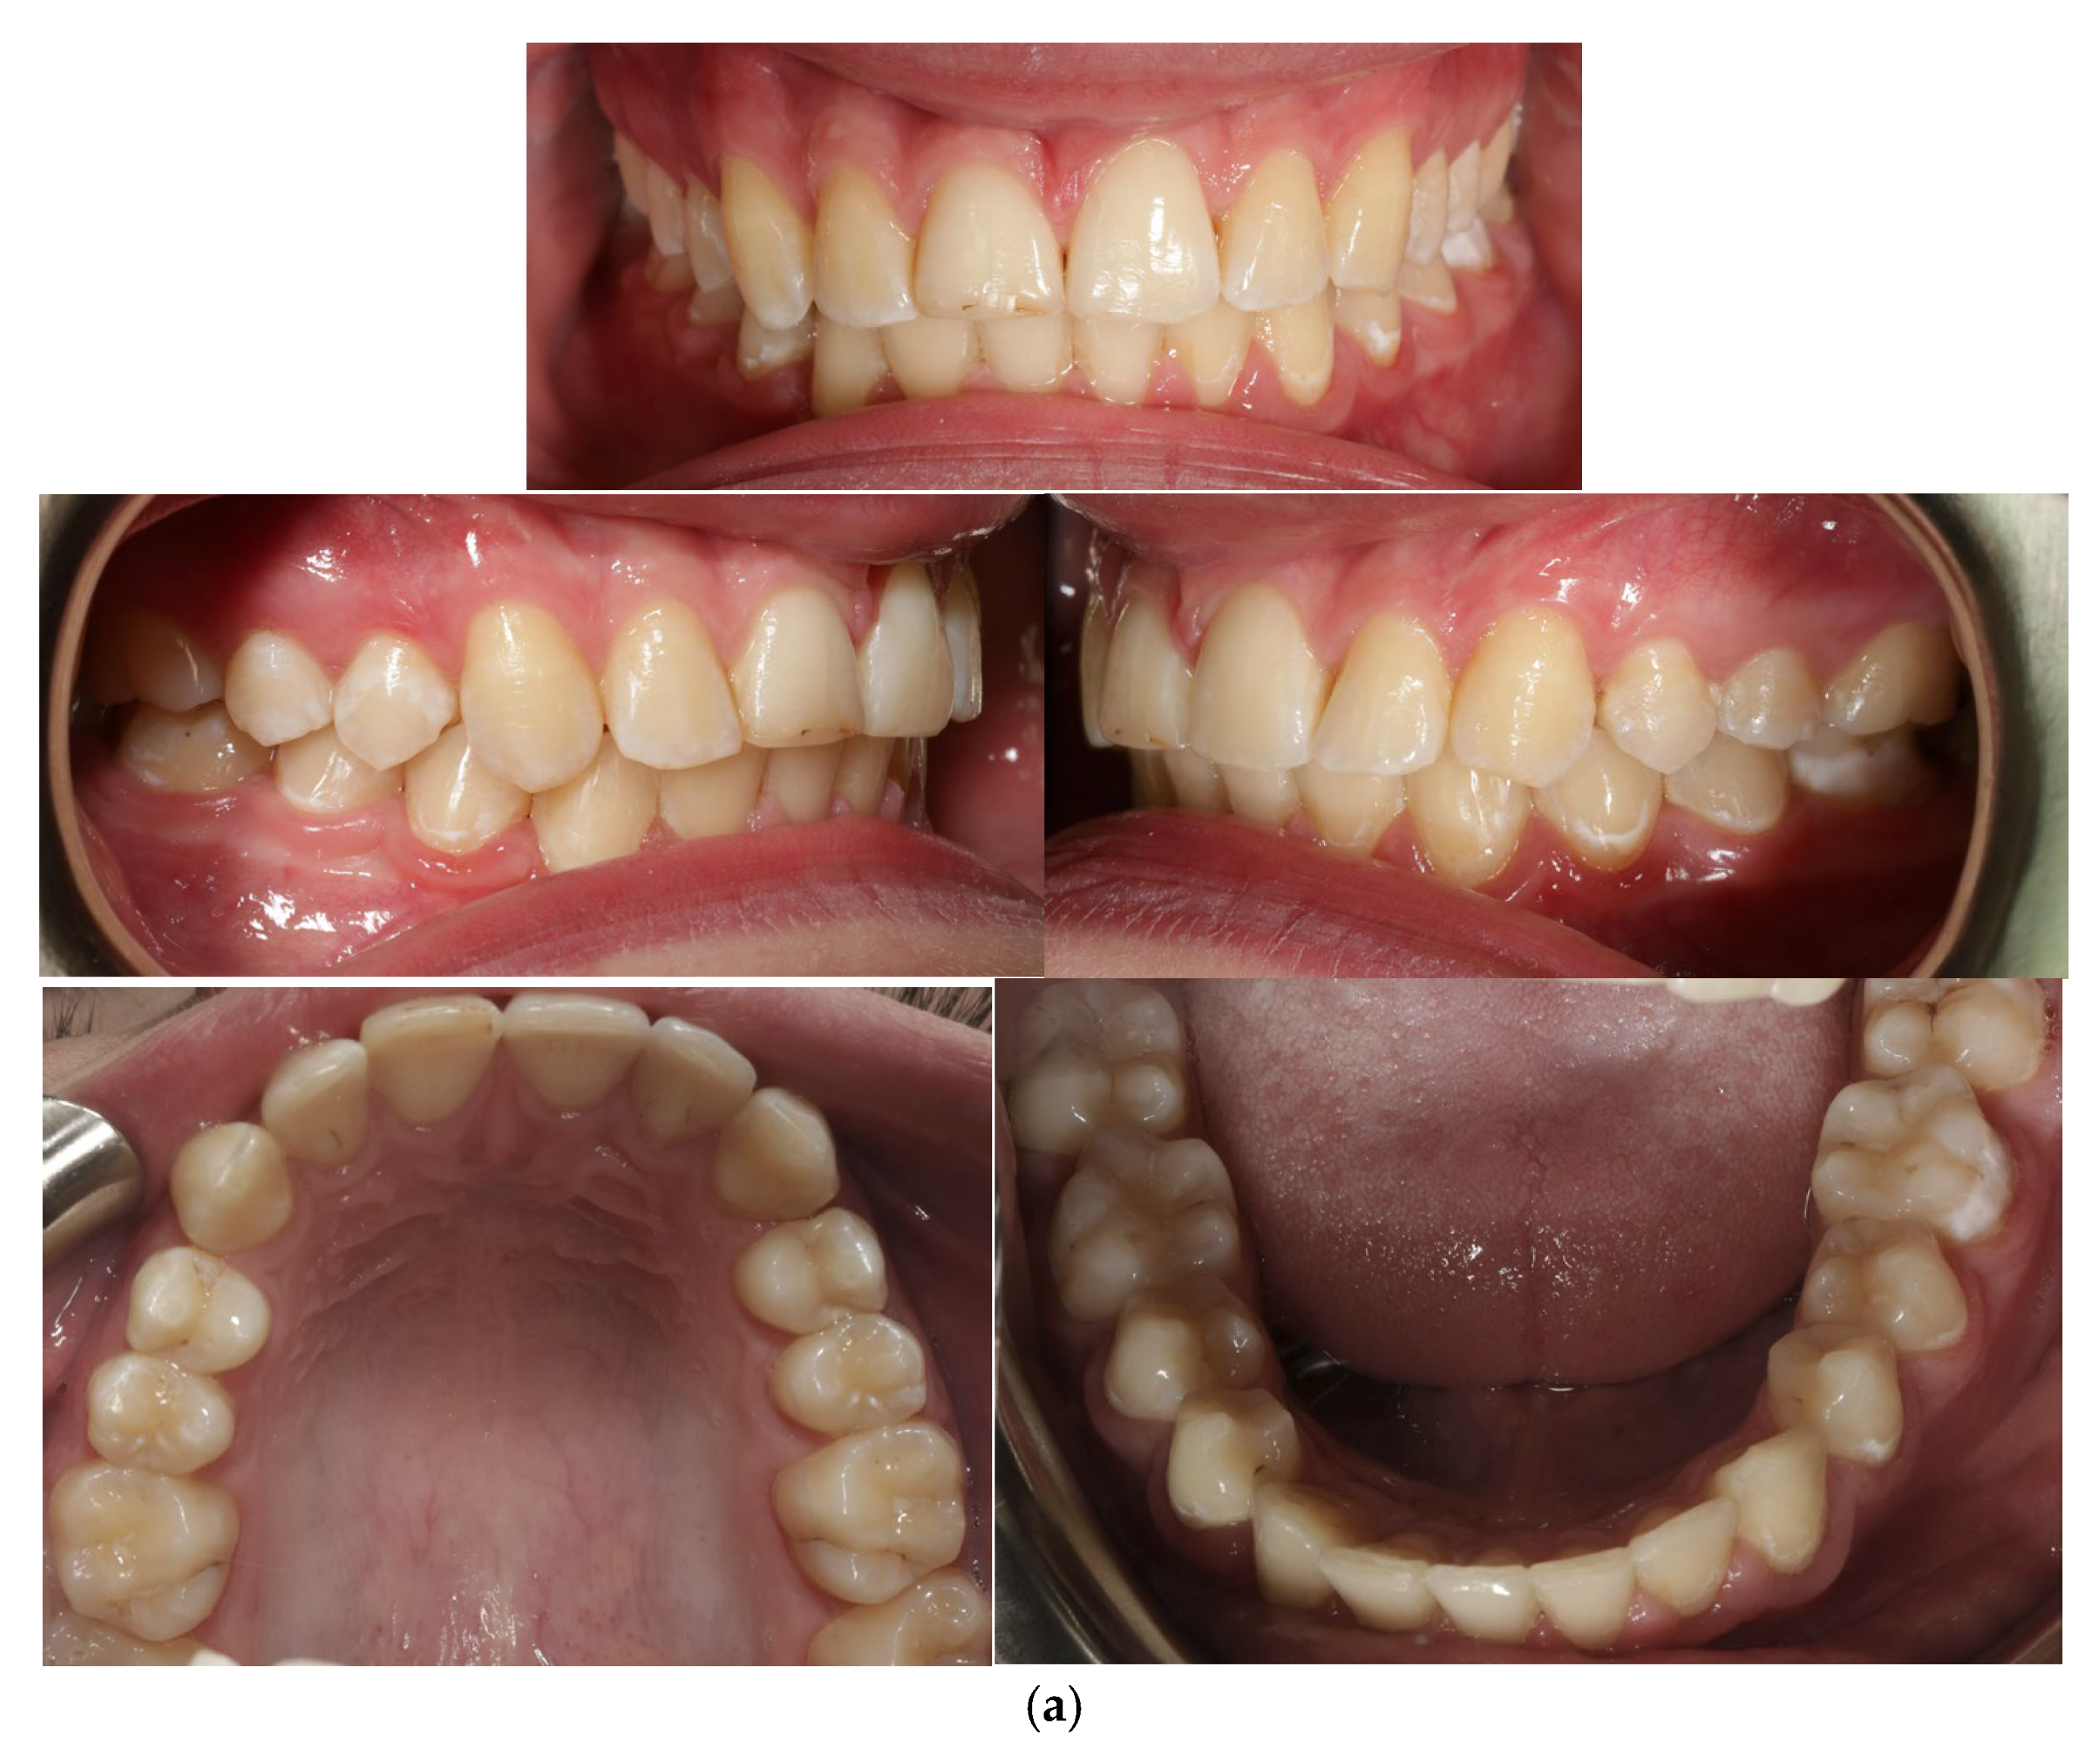

A 13-year-old patient presented with a horizontally impacted lower right canine located beneath the apices of the lower incisors, exhibiting transmigration. The patient had Angle Class I occlusion with no significant dental abnormalities (Figure 1). Following a detailed analysis of the CBCT scan of the mandible (Figure 2), a decision was made to recreate space within the arch and reposition the impacted canine. Given the close proximity of the canine to the roots of the lateral incisors, precise orthodontic traction guidance was required.

Figure 1. Photos before treatment: (a) extraoral, (b) intraoral and (c) models.